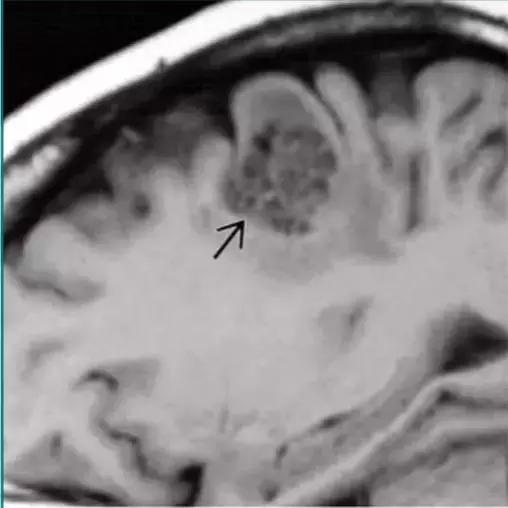

肿瘤相关良性囊肿